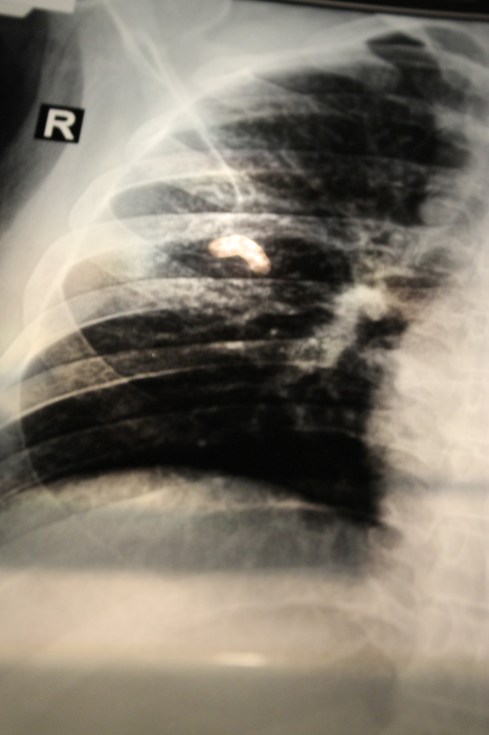

Bones begin to return from the abyss of british excess. I feel them as i fall out of a rickshaw onto the road. Pelvis and stitches to the left, breast bones to my heart and a rib cage i can see again under a not so distant surface. Nothing broken and still time for the skeleton to rise.